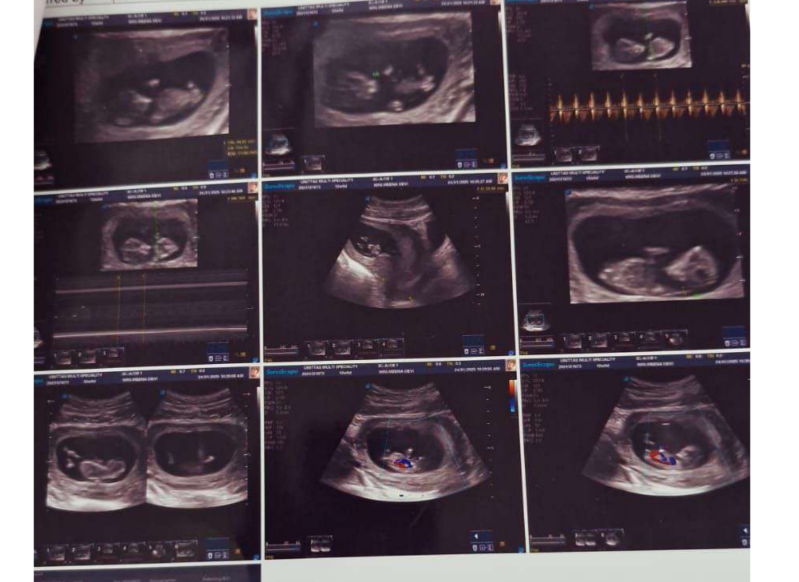

She had been diagnosed with PCOS. Her ultrasound showed bilateral polycystic ovaries: multiple peripherally placed small follicles on both sides. Her AMH was 12.13 ng/mL: significantly higher than the normal range for her age, a hallmark of PCOS.

Throughout all 40 weeks, her thyroid stayed in range. No gestational diabetes. Blood pressure normal. She completed her pregnancy smoothly, with no complications.

- She went through 40 weeks with normal thyroid, sugar, and BP: no complications, with nutrition, yoga, and mental health support throughout

We’ve blurred this image to protect the family’s privacy. But that little blur is the most meaningful thing we’ve ever been a part of.